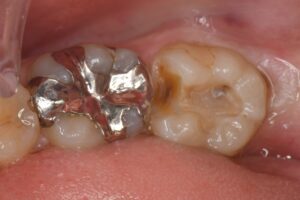

検診をクリーニングを希望されて来院された方です。今までこまめに歯科医院に通われていたそうですが、レントゲンを撮影していなかったそうで、この度レントゲン写真にて保険の白い詰め物の下に大きな虫歯が見つかったため、ご本人様に治療の必要性と治療の選択肢、それぞれのメリットデメリットをお話ししたところ、患者様は一番良い治療で治したいとのことでしたので、再発率が最も少なく、歯をできるだけ削らないe-maxでの治療を行うこととしました。

すずき歯科・矯正歯科では、年1回のパンラマレントゲン写真は必ず撮るようにしており、隠れた虫歯を見逃さない覚悟で日々の診療を行なっております。

赤い点で、事前に噛む場所を確認しています。虫歯以外の場所で噛んでいないようならe-max治療は行えないためです。